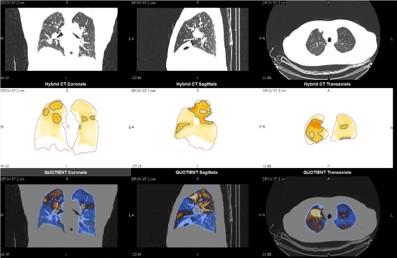

8. 肺換気・血流ソフトウェア解析による定量評価

肺換気・血流2核種同時撮影のメリットを生かし換気/血流/ミスマッチ画像が一度に得られ、読影がしやすくなっている。ワークステーションのQ.Lung AIソフトウェアによりミスマッチ画像とのCT FusionやCTで区域分けを行い各肺野領域ごとでの体積とカウントの数値の割合を定量値として表示できる。CTEPH治療前後でのミスマッチ率の評価も、どの程度改善したのか定量化し客観的に評価する機能も備わっており、今後このような指標を使って研究的な所に加えて臨床応用ができるものと期待される。

StarGuide_Keio15.jpg

多発性肺塞栓例におけるミスマッチ、Fusion画像

StarGuide_Keio16.jpg

各肺野領域における体積とカウント結果画面